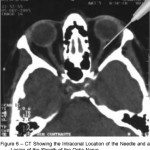

En el estadio terminal de muchas enfermedades oculares, como el glaucoma terminal, cuando se ha perdido la visión y el ojo manifiesta un dolor importante, una de las opciones de tratamiento es la inyección retrobulbar. El objetivo de este estudio, publicado en el número de noviembre de de 2016 de la revista Journal of glaucoma fue evaluar 2 agentes utilizados en las inyecciones retrobulares para aliviar el dolor en ojos amauroticos dolorosos.

glaucomaEl estudio comparó las inyecciones retrobulbares en pacientes, que se dividieron en 2 grupos: los ojos del grupo 1 (GI) recibieron 1,5 ml de alcohol absoluto (etanol) y los del grupo 2 (G-II) De clorpromazina (25 mg / ml). El dolor se clasificó antes, durante y después de la intervención. También se registraron la presión intraocular y los eventos adversos. El éxito completo se definió como ningún dolor después de la inyección. Los fracasos del tratamiento se clasificaron como intervención adicional (evisceración-enucleación) o si no se modificaron las puntuaciones de dolor.